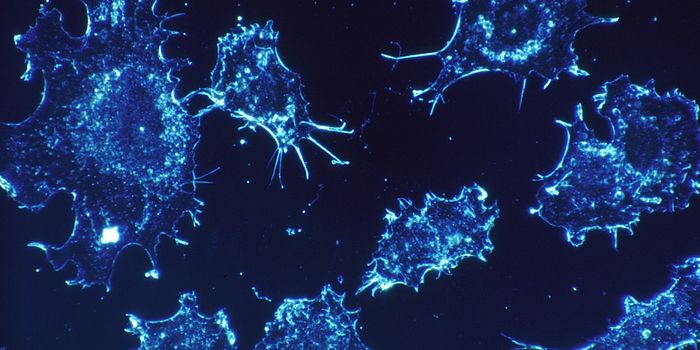

DEC 16, 2019Cell & Molecular BiologyCancer becomes most deadly when it has metastasized - when cancerous cells move away from the site where cancer started ...